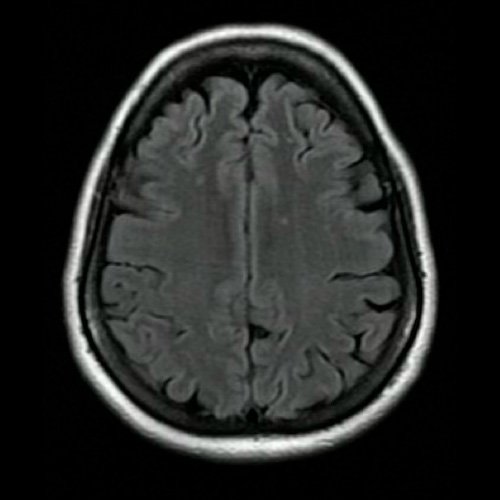

Anexo 2. Angio RMI de cráneo: Corte transversal. Secuencia t2 flair

• Angio RMI de cráneo (Dia 2):  Se visualizan lesiones en la sustancia blanca subcortical de centros semiovales y coronas radiadas, hiperintensas en T2/FLAIR, sin restricción en difusión/ADC, de aspecto inespecífico. Podrían estar en relación a trastorno de la microvasculatura, de larga data.  Las regiones ganglio basales son de características habituales. El sistema ventricular supratentorial es de forma tamaño y situación normal.En la fosa posterior el 4º ventrículo es de forma tamaño y situación normal. No se observan alteraciones en la intensidad de la señal hemisferios cerebelosos  los cuales son de morfología habitual.  El tronco encefálico no mostró alteraciones. En la secuencia angiográfica 3D TOF se observa dilatación sacular en la porción inferior del segmento supraclinoideo de la arteria carótida interna izquierda, que mide 2.2 mm, con un cuello de 2.6 mm. Agenesia arteria comunicante posterior izquierda. Las restantes estructuras vasculares del polígono de Willis, son de trayecto calibre y señal flujo conservados, no identificándose alteraciones.